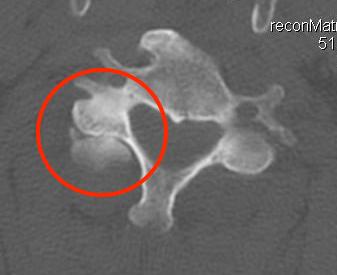

Unilateral facet joint dislocation on CT

Bilateral jumped facets on CT